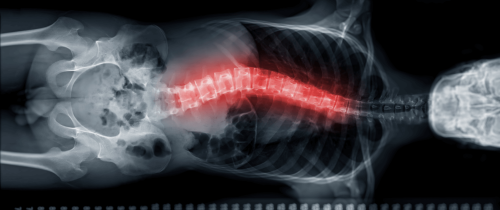

Scolioza idiopatică este o deformare a coloanei vertebrale care apare fără o cauză cunoscută. Aceasta înseamnă că o porțiune a coloanei se curbează lateral și se rotește ușor, modificând postura și aspectul spatelui. Se definește printr-o curbură de cel puțin 10 grade, observată pe radiografie. Apare cel mai frecvent în perioada adolescenței, în timpul creșterii rapide, și nu este cauzată de o boală, un accident sau o problemă congenitală.

Scolioza reprezinta o modificare tridimensionala a coloanei vertebrale cu doua, trei sau chiar patru curburi, deformare care se poate observa chiar si cu ochiul liber daca privim spatele unei persoane. Mai sunt si alte indicii la care ar trebui sa fie atenti parintii in diagnosticarea scoliozei la copii?